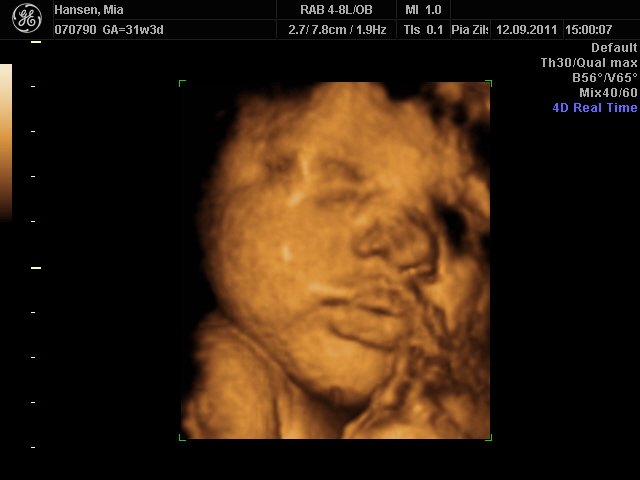

Hun er stadigvæk en rigtig putterøv, men vi fik en masse smil og trut-munde af hende

hun har lange øjenvipper og hår i nakken